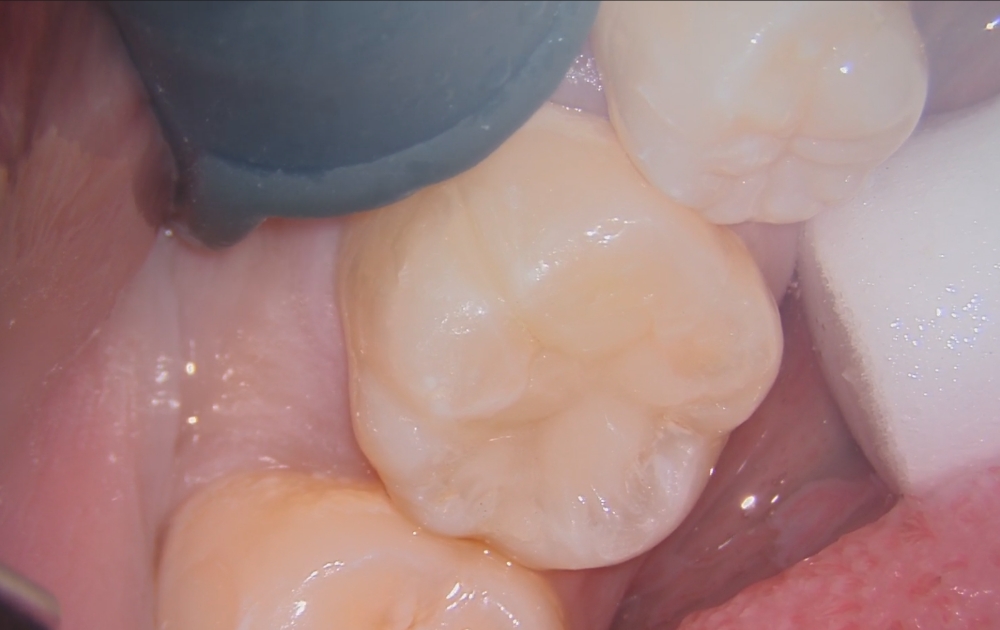

• 9.おおよその充填が完了した状態です。形が整ってきた段階で、噛み合わせや周囲との調和を確認します。

• 10.噛み合わせを調整し、形態修正と研磨を行って仕上げます。最後に細かい部分を整え、滑らかになるよう研磨して治療完了です。

9.おおよその充填が完了した状態です。

形が整ってきた段階で、噛み合わせや周囲との調和を確認します。

10.噛み合わせを調整し、形態修正と研磨を行って仕上げます。

最後に細かい部分を整え、滑らかになるよう研磨して治療完了です。